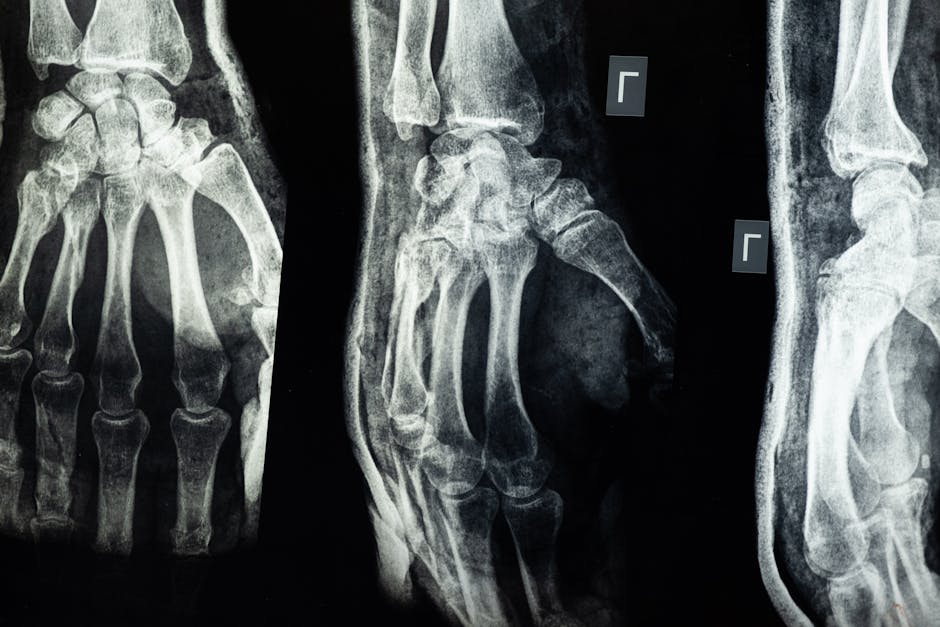

Fracture risk assessment in Sweden has taken a significant leap forward, with a new study from the University of Gothenburg revealing that the current risk estimates are overinflated. This overestimation, based on outdated data, could lead to unnecessary treatments and misallocations of healthcare resources. The study, published in the Journal of Bone and Mineral Research, highlights the need for a more accurate and up-to-date tool to assess the 10-year risk of osteoporotic fractures, particularly as demographic changes and improvements in healthcare have altered the landscape.

The Fracture Risk Assessment Tool (FRAX) is a widely used algorithm that calculates the 10-year probability of hip fracture and major osteoporotic fractures (vertebral, forearm, hip, or shoulder) based on clinical risk factors. However, the Swedish version of FRAX relies on data from the 1990s, a period marked by significantly different population demographics and healthcare practices. The overestimation of fracture risk, as identified by the University of Gothenburg study, underscores the critical need for updating the model to reflect current conditions and prevent overmedication and resource wastage.

The overestimation of fracture risk has significant implications for healthcare policy and practice. According to the study, the current FRAX model in Sweden overestimates the 10-year risk of hip fractures by up to 30% in certain age groups. This discrepancy is attributed to the outdated data, which does not account for improvements in bone health, changes in lifestyle, and advancements in medical care. The researchers propose updating the model with the latest data, which would not only improve accuracy but also help in the allocation of healthcare resources to those who need them most. The updated model could reduce the number of people receiving unnecessary treatment, thereby lowering healthcare costs and improving patient outcomes.